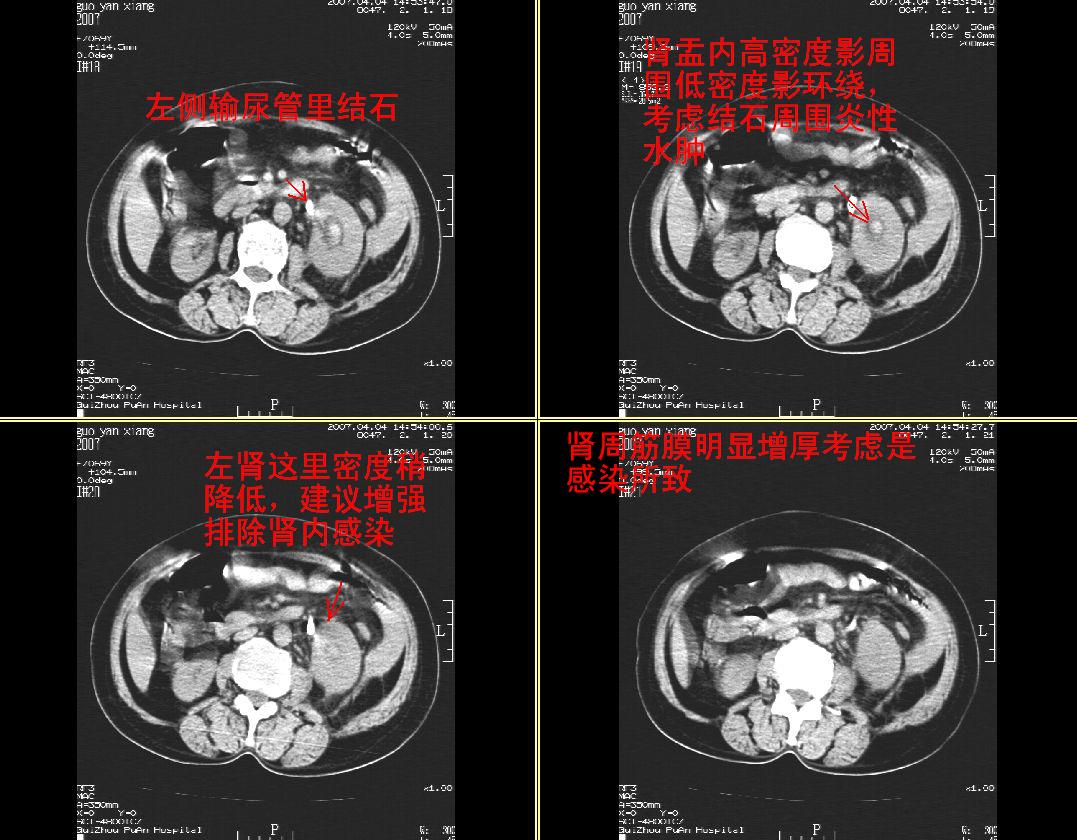

女性,59岁,腰痛,腹痛3天,未见肉眼血尿

左肾体弥漫性增大,肾周脂肪间囊密度增高,侧锥筋膜明显增厚,肾盂内见高密度影,左输尿管隐约可见,密度似较高,病程短,考虑:左肾急性肾盂肾炎,左肾盂内积血。不知临床还有没有其它相关体征及实验室检查?

肾周筋膜是增厚,肾盂内可见高密度影,但肾盂下部近输尿管处还是可见结石影。

左肾及输尿管上端结石。

支持:1、左侧输尿管上端结石伴肾盂积血、肾感染;

2、建议增强扫描进一步检查。

左肾及输尿管上端结石,伴左肾积水 积血。

左肾及输尿管上端结石伴肾盂积血、肾感染,建议增强.

支持:左肾及输尿管上端结石,伴左肾积水, 积血,合并感染.

左肾弥漫性增大,肾盂内见略高密度影,肾盂无明显扩张,肾实质密度均匀,肾周脂肪间囊密度增高,侧锥筋膜明显增厚,病程短,考虑:左肾急性肾盂肾炎,肾周感染,左肾盂内积血。建议完善相关检查或抗炎治疗后复查。